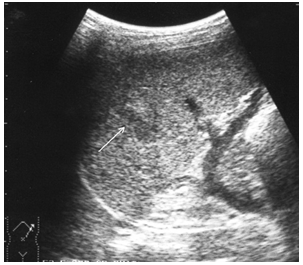

Чрескапсульные разрывы селезенки манифестируют нарушением непрерывности контура органа и визуализацией внутриорганных линий разрыва (рис. 7). Последние представляют собой гипоэхогенную или эхонегативную, в зависимости от времени, прошедшего после травмы, зону линейной или «ветвистой» формы с неровными и нечеткими контурами. Важно отметить, что прямые эхографические признаки, будучи патогномоничными для данного вида повреждений, не имеют облигатный характер. В частности, нарушение непрерывности контура селезенки наблюдается только у 25,4 % больных, а линия внутриорганного разрыва визуализируется в 60,3 % случаев. При этом возможность выявления указанных признаков в ранние сроки весьма проблематична и становится реальной только через 16–24 часа после травмы.

Рис. 7. Эхограмма чрескапсульного разрыва селезенки. Нарушение непрерывности контура указано стрелкой.

В связи с вышеизложенным особое клиническое значение приобретают косвенные эхографические признаки чрескапсульного разрыва органа, прежде всего внутрибрюшинного кровотечения, отмеченного у всех больных с таким характером травмы. Периспленическая гематома (рис. 8) представляет собой околоорганное скопление крови, полностью либо частично окружающее поврежденную селезенку и ограниченное такими анатомическими образованиями, как купол диафрагмы, задний листок париетальной брюшины, петли кишечника, фиксированные пряди большого сальника и т. д.

Следующим по значимости и частоте выявления косвенным эхографическим признаком чрескапсульного разрыва селезенки стала визуализация ткани большого сальника, фиксированного в зоне повреждения или окутывающего весь орган (рис. 9).

Рис. 9. Эхограмма чрескапсульного разрыва селезенки. Фиксированная прядь большого сальника указана стрелками.

Фрагментация (отрыв полюса) селезенки представляет, по сути, частный вариант чрескапсульного разрыва с полным разобщением фрагментов органа. Наряду с раздельной визуализацией фрагментов выявляются линии разрывов и вышеописанные косвенные признаки, характерные для данного вида повреждений (рис. 10).

Рис. 10. Эхограмма полного поперечного разрыва селезенки. Линия разрыва указана стрелками.